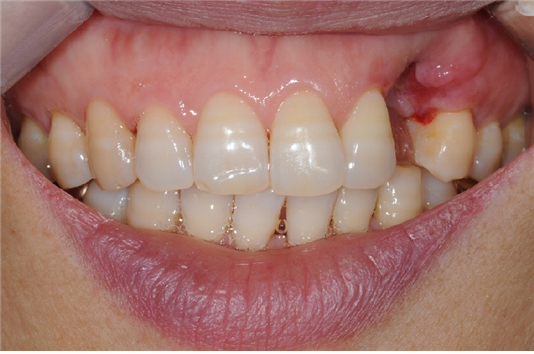

위 환자분은 타 치과에서 발치 후 어색해 보이지 않게 임플란트를 하고 싶다고 하시며 내원하셨습니다. 내원 당시 발치를 하고 잇몸 회복이 잘되지 않아서 잇몸이 위로 많이 올라간 상태였습니다. 발치 전 환자분의 치아 상태는 알 수 없었으나, 발치한 부위의 치조골 소실과 연조직 손상이 심했습니다.

이 상태로 바로 전주신시가지치과에서 앞니임플란트 식립을 하게 되면 치아머리 부분에 해당하는 보철물이 길게 제작되어 심미적으로 좋지 않은 결과가 예상되는 상황이었습니다. 본원에서는 뼈 이식 없이 이대로 치유 후 간단한 연조직 시술을 통한 최소침습 방법으로 전주신시가지치과에서 앞니임플란트 수술 계획을 세웠습니다.